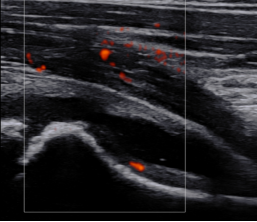

四、超声检查在儿童髋关节滑膜炎中的应用[2]

超声检查是一种无创、无辐射的检查方法,对于儿童髋关节滑膜炎的诊断具有重要价值。通过超声检查,可以观察到髋关节内的积液情况、滑膜的厚度以及关节周围组织的病变情况,为临床诊断提供依据。

3. 能够观察关节内积液、滑膜厚度和形态等细节,为诊断提供依据。

2. 对于积液较多的患儿,可在超声引导下进行关节穿刺,以减轻关节肿胀和疼痛。